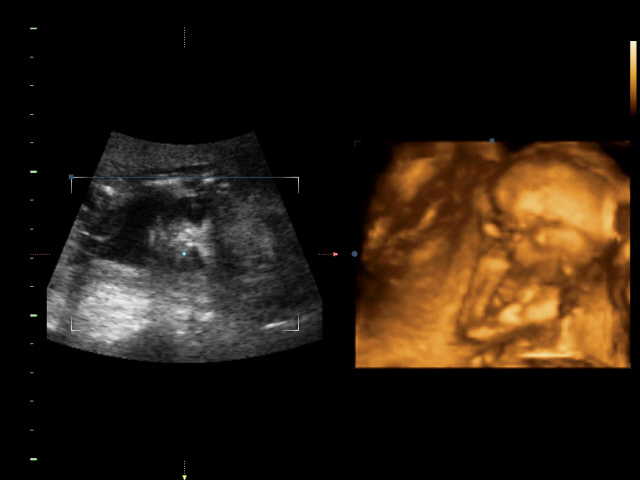

УЗИ, КТГ, доплерСходили всей семьей на 4D УЗИ! Определили нам пол окончательно и бесповоротно! Мальчик! Показали писюн! Так здорово! Я просто поверить не могу! А ведь он мне два раза снился! Настоящий реальный мужчина! Все показатели у нас в норме.